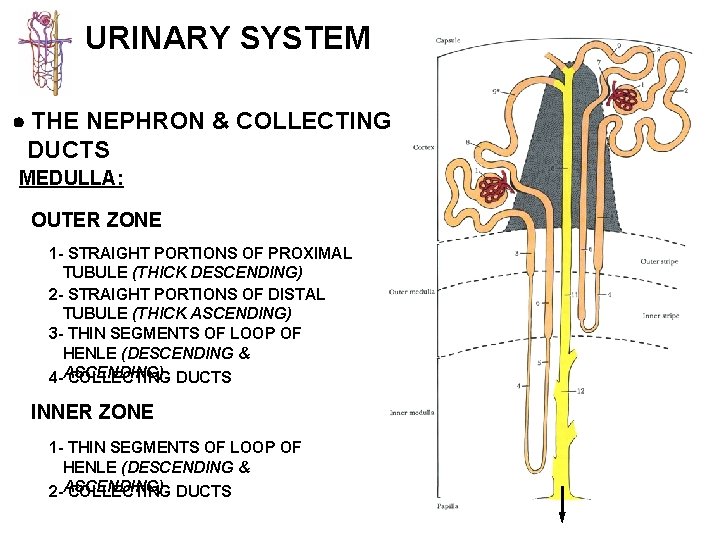

URINARY SYSTEM THE NEPHRON & COLLECTING DUCTS MEDULLA: OUTER ZONE 1 - STRAIGHT PORTIONS OF PROXIMAL TUBULE (THICK DESCENDING) 2 - STRAIGHT PORTIONS OF DISTAL TUBULE (THICK ASCENDING) 3 - THIN SEGMENTS OF LOOP OF HENLE (DESCENDING & 4 -ASCENDING) COLLECTING DUCTS INNER ZONE 1 - THIN SEGMENTS OF LOOP OF HENLE (DESCENDING & 2 -ASCENDING) COLLECTING DUCTS

URINARY SYSTEM THE NEPHRON & COLLECTING DUCTS MEDULLA: OUTER ZONE 1 - STRAIGHT PORTIONS OF PROXIMAL TUBULE (THICK DESCENDING) 2 - STRAIGHT PORTIONS OF DISTAL TUBULE (THICK ASCENDING) 3 - THIN SEGMENTS OF LOOP OF HENLE (DESCENDING & 4 -ASCENDING) COLLECTING DUCTS INNER ZONE 1 - THIN SEGMENTS OF LOOP OF HENLE (DESCENDING & 2 -ASCENDING) COLLECTING DUCTS